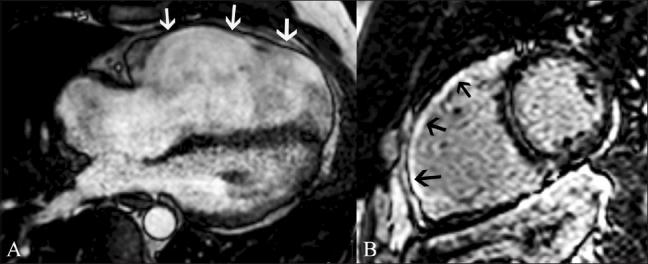

磁共振成像在评估心电图ST段抬高患者中的应用价值。

Utility of magnetic resonance imaging in the evaluation of patients with ST segment elevation on an electrocardiogram.

ST segment elevation is an important electrocardiographic (ECG) change that is typically found in acute myocardial infarction, but may also be seen in a variety of other conditions. MRI plays an important role in the evaluation of these patients. MRI not only establishes the diagnosis, which is essential for appropriate management, but also helps in the assessment of other factors that are important for risk stratification. In this review, we discuss the common and uncommon causes of ST segment elevation and the role of MRI in the evaluation of these disease processes.

摘要